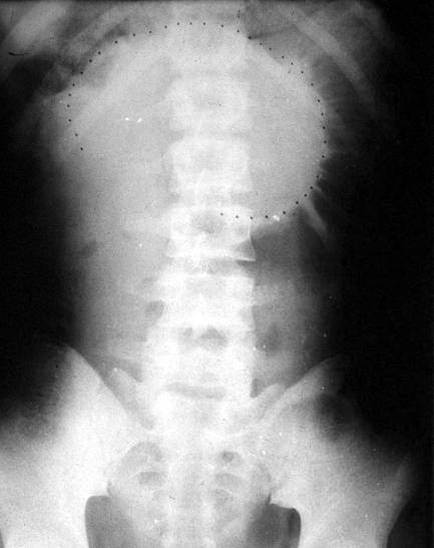

Bk72z.jpg

(434 × 548像素,文件大小:23 KB,MIME类型:

肠梗阻